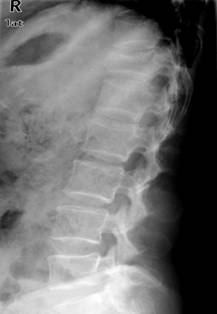

照片名称:胸椎压缩性骨折